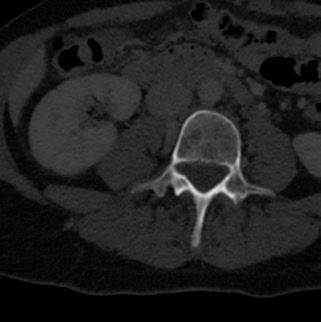

In particolare, GD viene sottoposta a

„ TAC torace e addome con mdc (figura 1): negativa per lesioni viscerali. Comparsa di alcune areole osteolitiche, di significato ripetitivo, a carico dell’emisoma destro di L4, all’ala iliaca di sinistra (la maggiore a livello della spina iliaca anteriore superiore con erosione della corticale ossea), a livello dell’osso pubico di destra con erosione della corticale ossea ed estensione verso la branca ischiatica omolaterale ed a livello della colonna posteriore dell’acetabolo di destra, con aspetto soffiato ed interrotto della corticale.